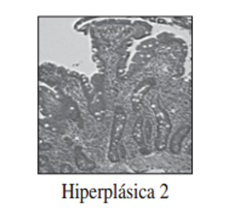

Imágenes tomadas durante la endoscopia digestiva alta y la colonoscopia. Se aprecia una mucosa de aspecto y vascularización normal, sin lesiones visibles. Se progresa con el colonoscopio hasta el íleon. Todo resulta macroscópicamente normal. Se toman biopsias de todos los segmentos explorados.

La endoscopia es el método de elección para el diagnóstico y seguimiento de la EII. Permite una visión macroscópica de la mucosa intestinal y la toma de múltiples biopsias para el estudio histológico.

Es la técnica de elección para diferenciar entre colitis ulcerosa (CU) y enfermedad de Crohn (EC), así como para localizar y valorar la extensión de la enfermedad.

Realizamos una endoscopia digestiva alta y una colonoscopia a la paciente con toma de biopsias, obteniendo el informe de Anatomía patológica.